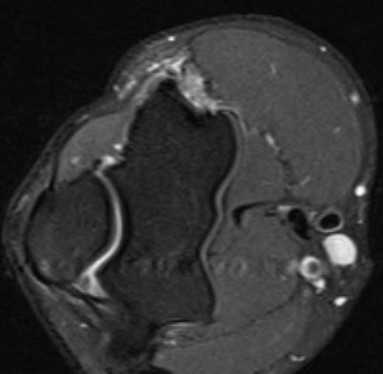

МРТ локтевого сустава в корональной плоскости. В подкожно-жировой клетчатке локтевого сустава отмечаются множественные образования неправильной вытянутой формы, местами сливающиеся между собой — вероятно, венозная мальформация.